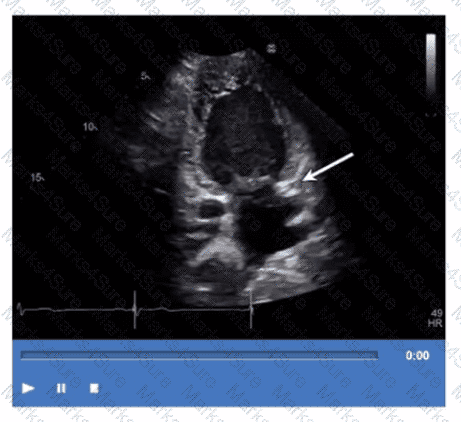

Which coronary artery territory is associated with the wall motion abnormality demonstrated in this video?